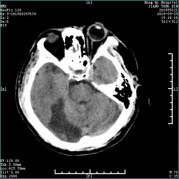

急性脑梗死的教学案例 专业知识 脑梗死(cerebral infarction,CI)又称缺血性脑卒中,是指各种原因所致脑部血液供应障碍,导致脑组织缺血、缺氧性坏死,而出现相应神经功能缺损的一类临床综合征。 案例 孙某,男,主因“发现言语不清、左侧肢体活动不灵1小时10分”入院。患者于14:30左右起床时发现言语含糊不清,吐字费力,口角歪斜,左侧肢体活动不灵,表现为左上肢无法抬起,左下肢无法行走,伴头晕,视物不适,无头痛,无恶心、呕吐,无视物旋转,无一过性黑矇,无意识障碍,无胸闷、气短。为求进一步诊治急来我院就诊。患者今日中午13:30睡午觉时无言语不清,无左侧肢体活动不灵。既往高血压病史10年余,平素血压最高达 210/120mmHg,未规律系统用药;否认心脏病、糖尿病病史。 查体:体温:36.5℃,血压:163/100mmHg,呼吸:20次/分,双肺呼吸音清,心率89次/分,腹软,双下肢无浮肿。神经系统查体:意识清,构音障碍,左侧瞳孔大约5.0mm,右侧瞳孔大约3.0mm,对光反射灵敏,水平眼震,左侧同向性偏盲,右侧头面部麻木,右侧周围性面瘫,伸舌居中,左上肢近端肌力2级,远端肌力2级;左下肢近端肌力3-级,远端肌力3-级,右侧肌力5级,四肢肌张力正常,腱反射(++),左侧Babinski(+),颈软,克氏征(-),NIHSS评分:9分。急查头部CT示:右侧枕叶低密度影。

立刻按静脉溶栓准备给予采血、心电、血压、血氧监护、吸氧。考虑患者为缺血性卒中,发病在溶栓时间窗内,但右侧枕叶低密度考虑为近期梗塞,静脉溶栓有一定出血风险,与患者家属沟通病情,交代溶栓利弊、告知可能出现的风险及预后。征得同意后给予静脉溶栓治疗(DNT:40min)。进一步行多模CT检查,发现患者椎基底动脉存在明显狭窄,建议溶栓后行桥接动脉取栓,患者家属拒绝。溶栓后患者肢体力量较前好转,溶栓24小时后给予抗血小板聚集、调脂稳斑、改善循环治疗,监测并控制血压。病情稳定后康复锻炼。出院时患者一般状态较前明显好转,左侧同向性偏盲,右侧头面部麻木,左侧肢体肌力5-级,右侧肌力5级。NHISS评分:2分,生活能够自理,对患者进行卒中二级预防教育,后随访患者预后良好。 脑梗死是神经科常见病,起病急骤,尤以后循环梗死病情凶险。神经系统体格检查对定位诊断具有重要意义,辅助检查DWI、MRA、CTA、DSA可以明确梗死部位、责任血管,对治疗方案确定、判断患者预后意义重大。 脑梗死急性期治疗包括静脉溶栓及动脉取栓,需根据患者病情严重程度及经济条件选择合适治疗方法,向患者及家属告知最优的治疗方案、提前预判可能出现的问题是一个合格神经科医生的责任,而合理有效的沟通是前提。 通过本案例学习,使学生掌握脑梗死引起神经功能缺失的表现,回顾神经解剖,了解神经系统查体的重要性,通过给出患者CT及MRI的结果,识别早期脑梗死的影像表现,了解脑血管的解剖,学习椎基底动脉系统梗塞的表现。拓展静脉溶栓及桥接治疗的意义及风险。 融入的思政教育元素 树立以病人为中心和以人为本的理念;注重医患沟通,根据患者经济情况选择合适的治疗方法;注重团队合作;提高对卒中的认识。 选择脑梗死作为PBL讨论课,因为它给人类健康造成严重危害,致残、致死率高,给患者及其家庭带来沉重的负担。通过此案例旨在让医学生了解处理急性脑梗死病人时要以同理心对待,把“时间就是大脑”牢记心间,注重团队合作精神,通过与急诊科、影像科、检验科、康复科等通力合作,共同挽救患者生命。 静脉溶栓及桥接治疗均存在一定风险,作为医学生应当了解可能的风险,提前判断预后,与患者家属沟通时,掌握沟通技巧,提前告知可能出现的风险,重要决定前需签署知情同意书,当患者拒绝有风险处置时应尊重患者意愿。静脉溶栓或桥接等治疗方案需要考虑患者经济条件及患者意愿。 2020年10月29日是第15个世界卒中日,今年宣传主题是“医体融合,预防卒中”,口号是“科学运动,健康生活”。在人文方面探讨卒中的预防,倡导运动与医学防治相结合,更好地防治卒中,高科技提供生活便利的同时,让人们的体能运动大大减少,而生命在于运动,“四体不勤”势必会给健康带来隐患。运动作为预防卒中、强身健体的良好预防方式,人人皆可行,这与健康中国行动计划不谋而合。推动体育与全民健身加入,预防卒中的行动是世界卒中组织的呼吁,也是中国政府的要求。重视医体融合预防,以实际行动实现健康中国的伟大梦想。 |